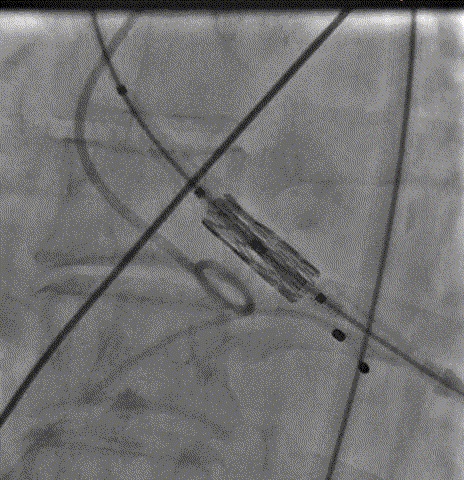

瓣膜定位后

快速起搏下5atm精准球扩释放21#Renatus瓣膜

释放后造影示瓣膜位置理想,形态良好